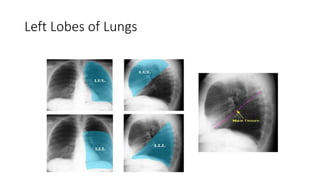

A normal chest x-ray shows the lungs, heart, bones, and soft tissues appearing healthy and unobstructed. The document discusses the different views used in chest x-rays, including PA, AP, lateral, and lateral decubitus views. It also covers topics like depth of inspiration, rotation exposure, the lobes of the lungs, identifying the heart, and how to read a normal chest x-ray.